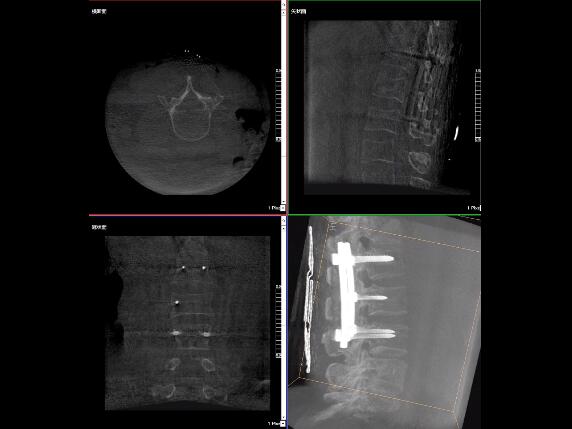

比如,醫(yī)生在做PKP(椎體成形術(shù))的時(shí)候,或者在置入螺釘?shù)臅r(shí)候,醫(yī)生需要在影像上看到螺釘打進(jìn)去的進(jìn)針點(diǎn)以及進(jìn)針的路徑。比如,我們?cè)诖蜓档尼斪訒r(shí)需要看到“貓眼”。我們只有把釘子完全打在“貓眼”里面,才能確保釘子打在了椎弓根里,所以對(duì)“貓眼”的顯影就非常重要。

“貓眼”指的是椎弓根在正位的投影。

最后我要強(qiáng)調(diào)一點(diǎn),以上我提到的“貓眼”,在二維的X光片上,醫(yī)生是靠經(jīng)驗(yàn)去判斷釘子是否打在椎弓根里,這個(gè)時(shí)候如果我們的設(shè)備再先進(jìn)一點(diǎn),診斷手段再多一點(diǎn),如果我們能夠把二維的影像轉(zhuǎn)換為三維的影像,可能就不會(huì)完全依賴醫(yī)生的經(jīng)驗(yàn)。

我們可以在三維的圖像中直觀的看到釘子到底在不在椎弓根里面,這樣可以指導(dǎo)我們準(zhǔn)確的進(jìn)針,指導(dǎo)我們進(jìn)行一場(chǎng)高質(zhì)量的手術(shù),可以起到事半功倍的效果,手術(shù)會(huì)簡(jiǎn)單得多,病人的預(yù)后也會(huì)好得多。